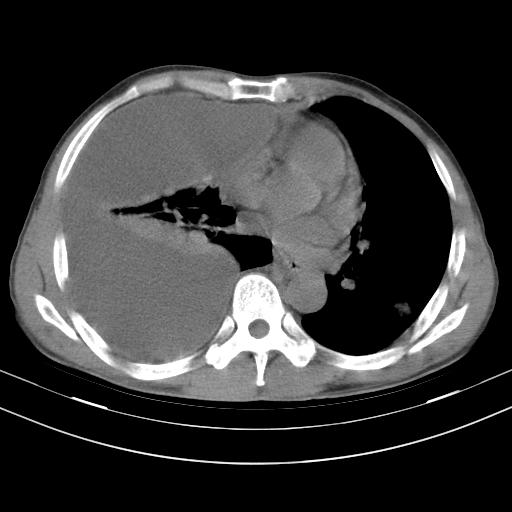

男性,44岁,结核病史多年。现胸闷气短,咳嗽,偶咳血。

右侧胸腔积液

右肺下叶不张

双肺多发结节影最分空洞形成考虑占位不除外结核

1、右侧大量胸腔积液伴右肺压缩性膨胀不全,建议抽液治疗后复查 2、两肺继发性tb伴空洞形成。

1)两肺继发性肺结核伴空洞形成,左肺多发性结核球。2)右侧大量胸腔积液伴右肺部分膨胀不全。3)纵隔淋巴结肿大。

吉大一院胸水抽检结果:结核性胸水